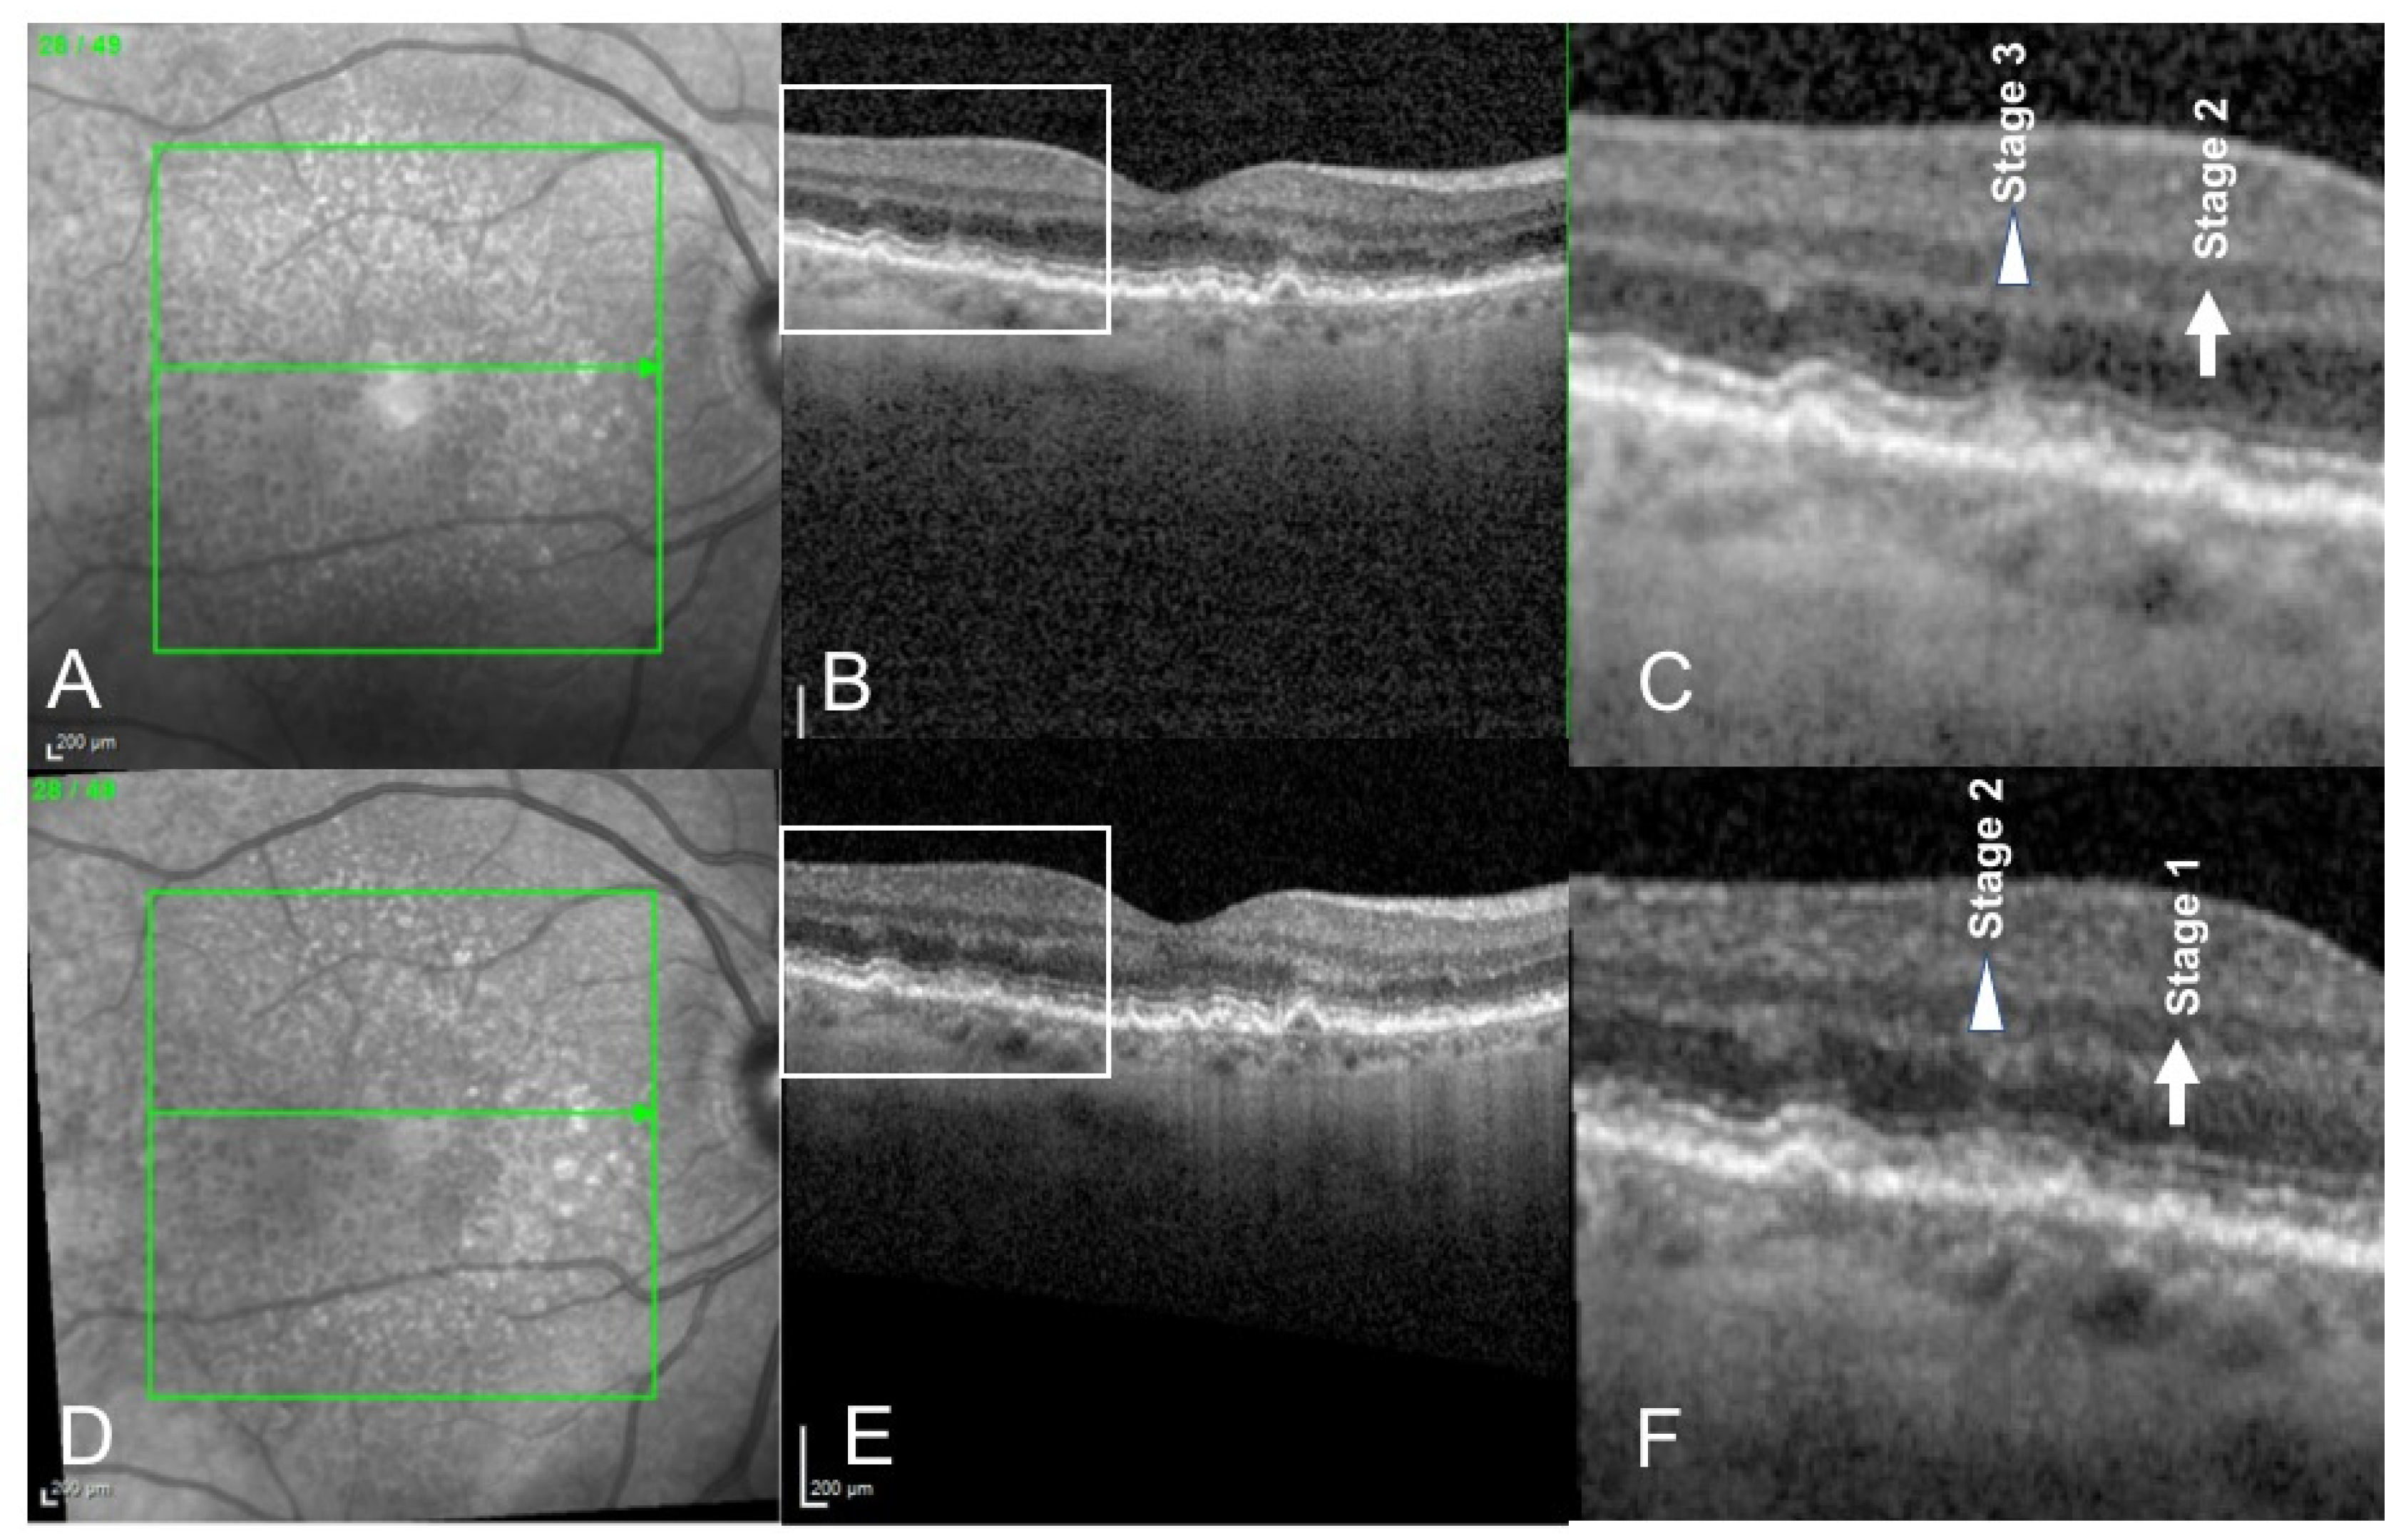

3. Results